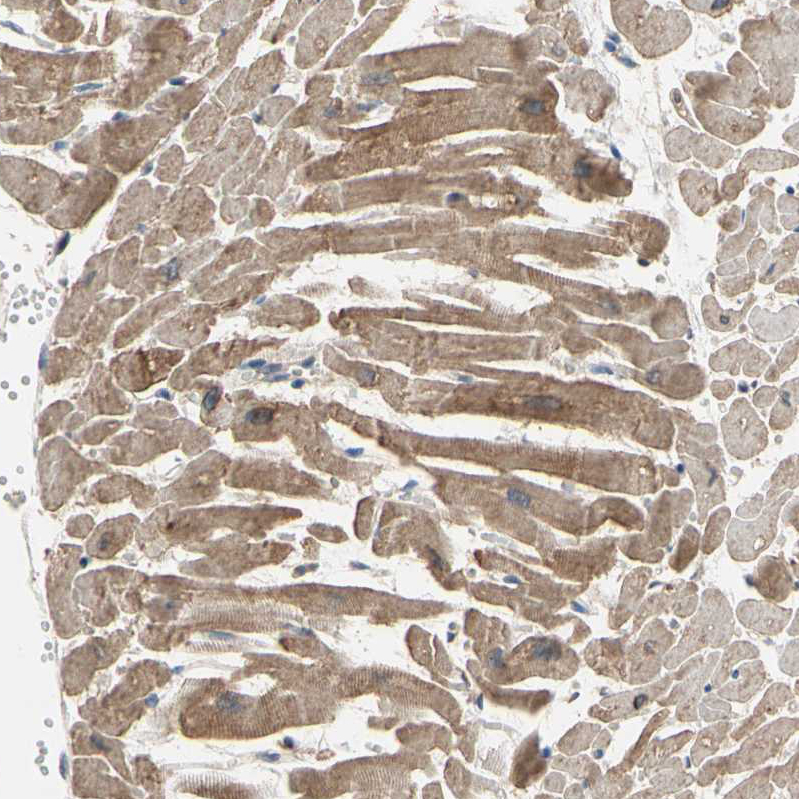

Immunohistochemical staining of human skeletal muscle shows strong cytoplasmic positivity in myocytes.